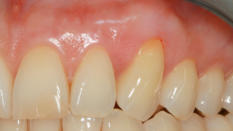

Zustand 3 Wochen post OP